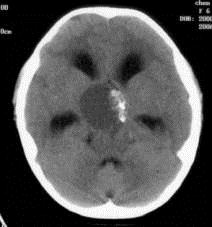

问题 病历摘要:??患者女性,6岁,半年来感觉视力模糊,近10天出现反复头痛,间有恶心呕吐,精神转差,查体:神志清楚,身高90cm,体重25Kg,血压90/55mmHg,右眼视力4.6,左眼视力4.8,双侧视乳头水肿,颈软,伸舌居中,四肢肌张力正常,肌力5级,双侧Babinski征(-)。 入院检查头部MRI,如图所示,诊断有可能是?

选项 A.垂体腺瘤 B.生殖细胞瘤 C.颅咽管瘤 D.视神经胶质瘤 E.蛛网膜囊肿 F.鞍结节脑膜瘤 G.脑积水

答案 CG